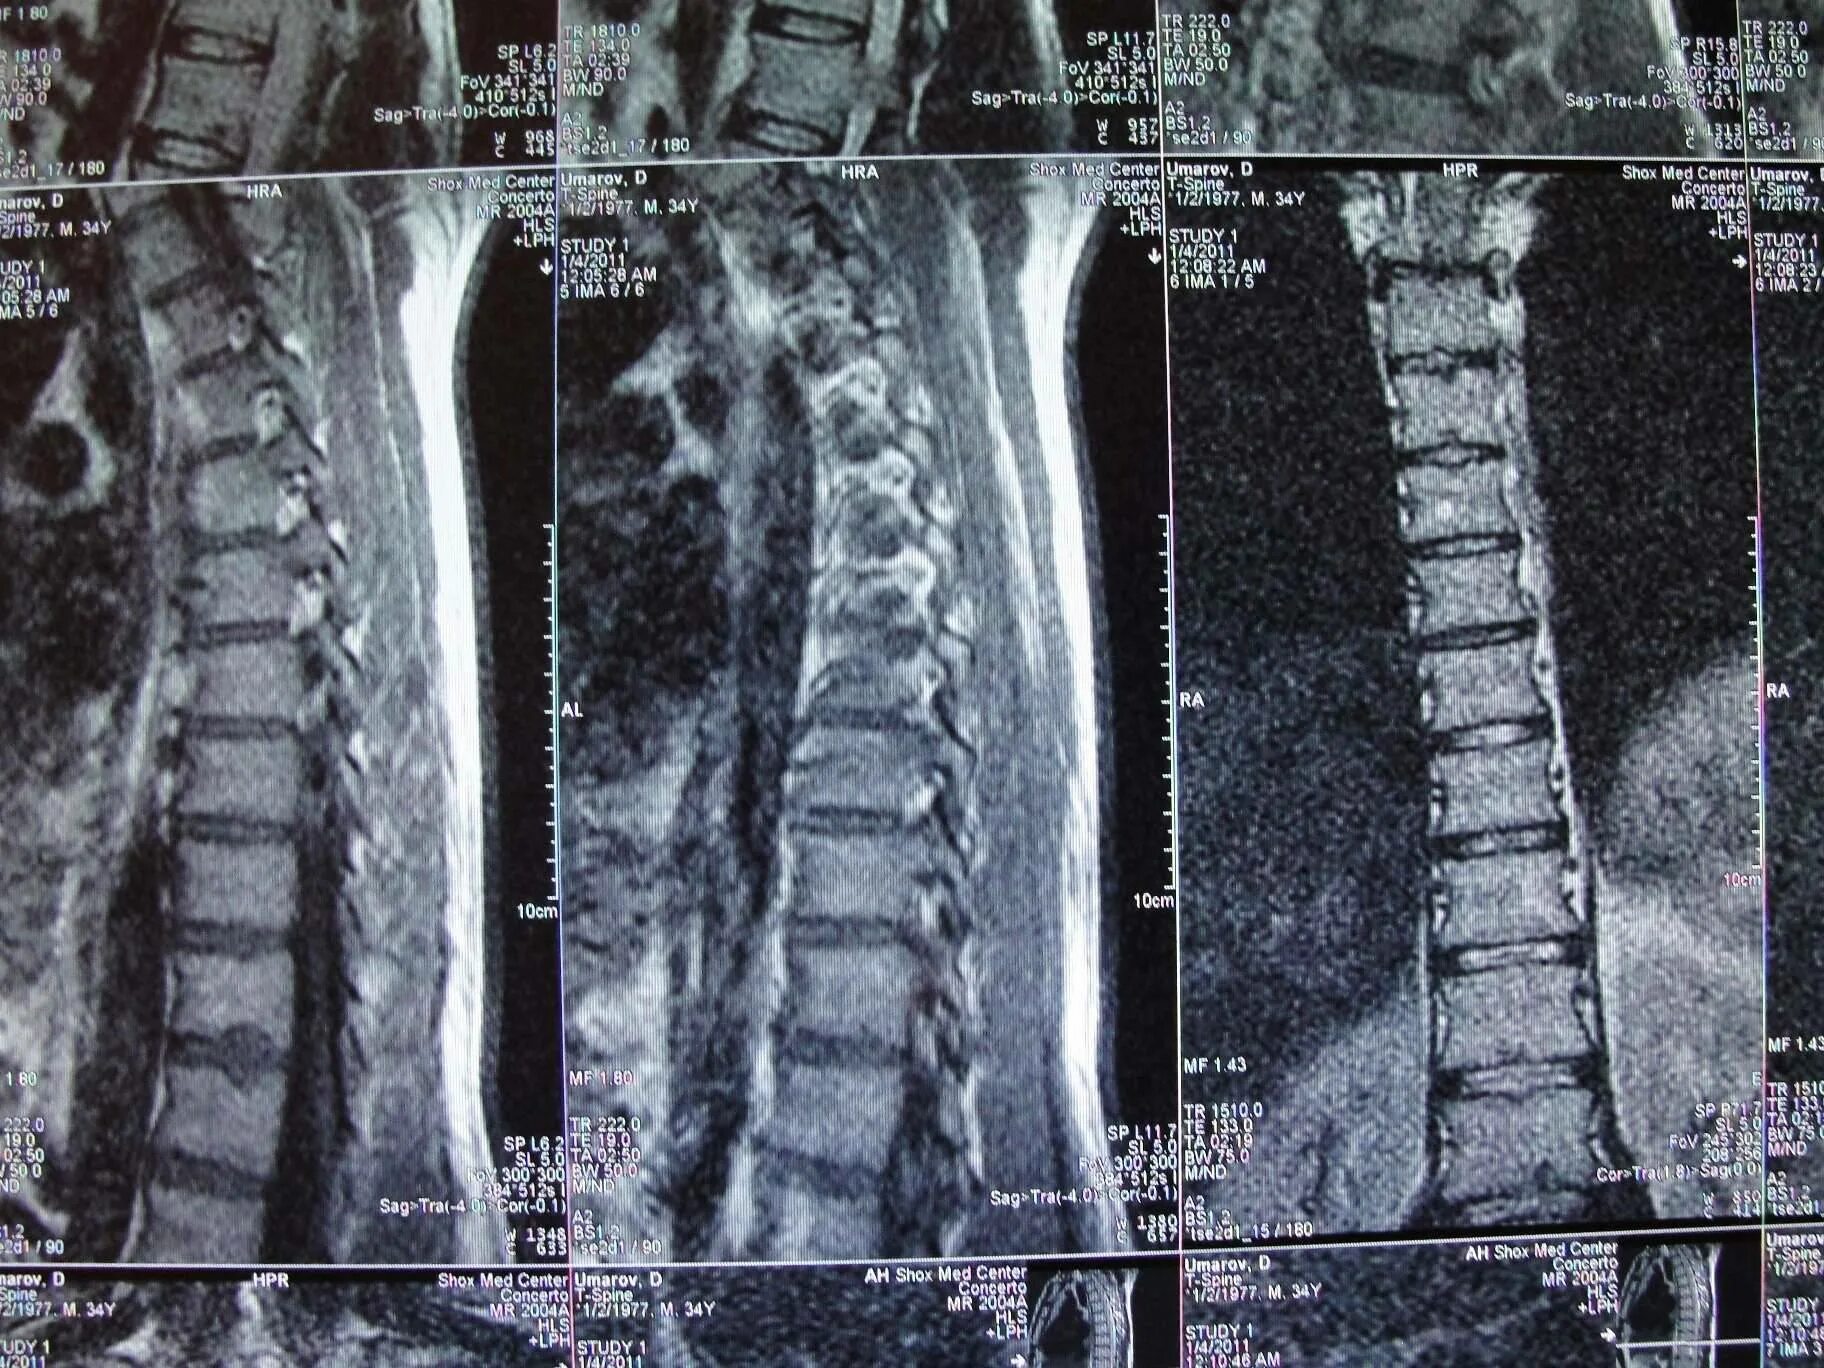

Как лечить грудную грыжу позвоночника